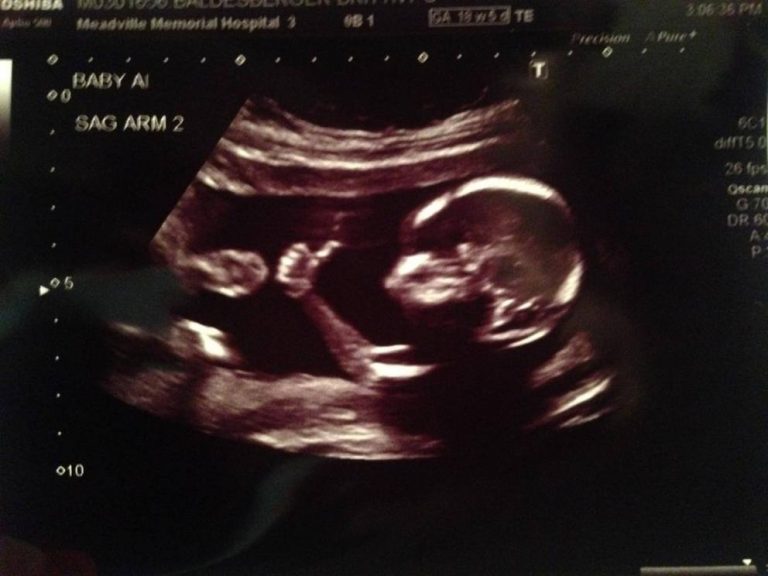

Davanti alla foto di un figlio che dal grembo materno quasi saluta il nostro corposo elenco di parole si rivelerebbe subito per quello che è: un cumulo di menzogne per rendere l’aborto procurato meno grave e la nostra coscienza più pulita